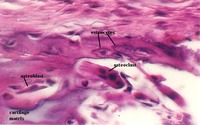

- Cartilage

- Endochondral bone development

- Intramembranous bone

development

- Compact Bone histology

- Cartilage and Bone cells